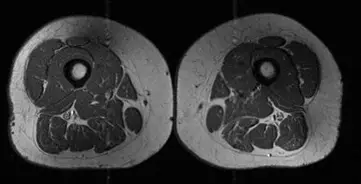

The first image shows a woman whose thigh muscles have minimal fat infiltration. She has a diet of 30 percent UPFs.

The second image shows a woman's thighs with greater marbling, and her diet consists of 87 percent UPFs.

Researchers found that greater consumption of UPF was linked to more apparent ‘marbling’, which describes when fat accumulates within the thigh muscles themselves and replaces healthy muscle tissue, leading to muscle weakening.

An MRI scan was done on each participant’s thighs, and researchers analyzed the scans and graded fat infiltration in the thigh muscles, including the hamstrings, quadriceps and inner thighs, on a scale from zero, which was no fat, to four, meaning greater than 50 percent fat.